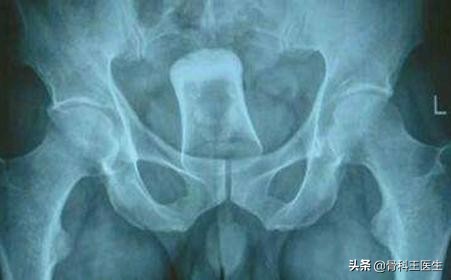

5、阴道、尿道取异物:

负责任的讲,肛门能进去的阴道都能塞进去:

我只发两张图,笑笑不说话: